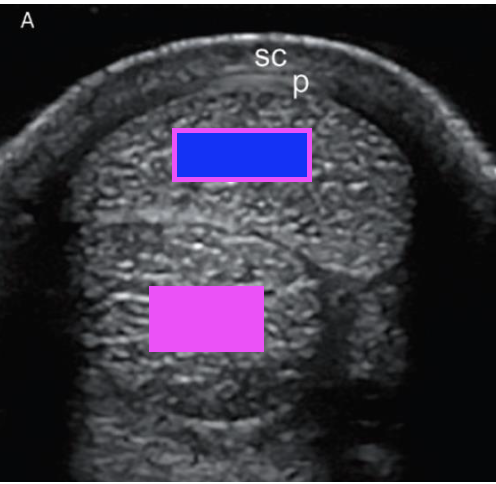

what type of ultrasound scan is shown?

transverse scan

what structure does the pink box indicate?

deep digital flexor tendon

what structure does the blue box indicate?

superficial digital flexor tendon